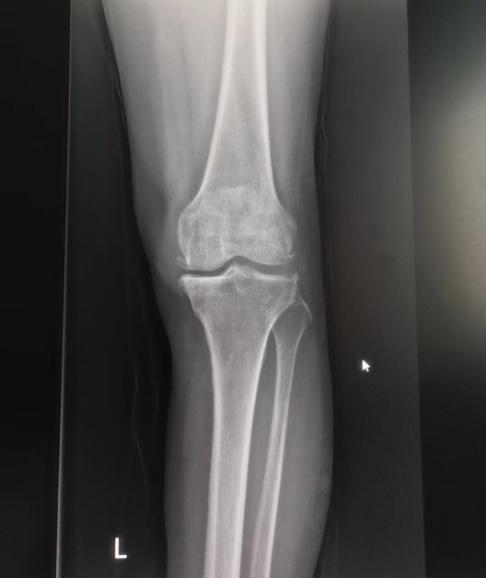

退行性骨关节炎,俗称“骨质增生”或“长骨刺”,是一种与年龄增长密切相关的关节疾病。其发病过程如下:随着年龄增长,或受关节受伤、基础疾病影响,关节软骨会逐渐退化、失去弹性,进而出现裂缝、糜烂甚至溃疡,表面变得粗糙;不光滑的软骨在关节活动中相互摩擦,会进一步加剧软骨损伤;当软骨完整性被破坏后,下方骨骼因失去保护而承受异常压力,便会通过增生形成“骨刺”来代偿,最终引发骨关节炎。